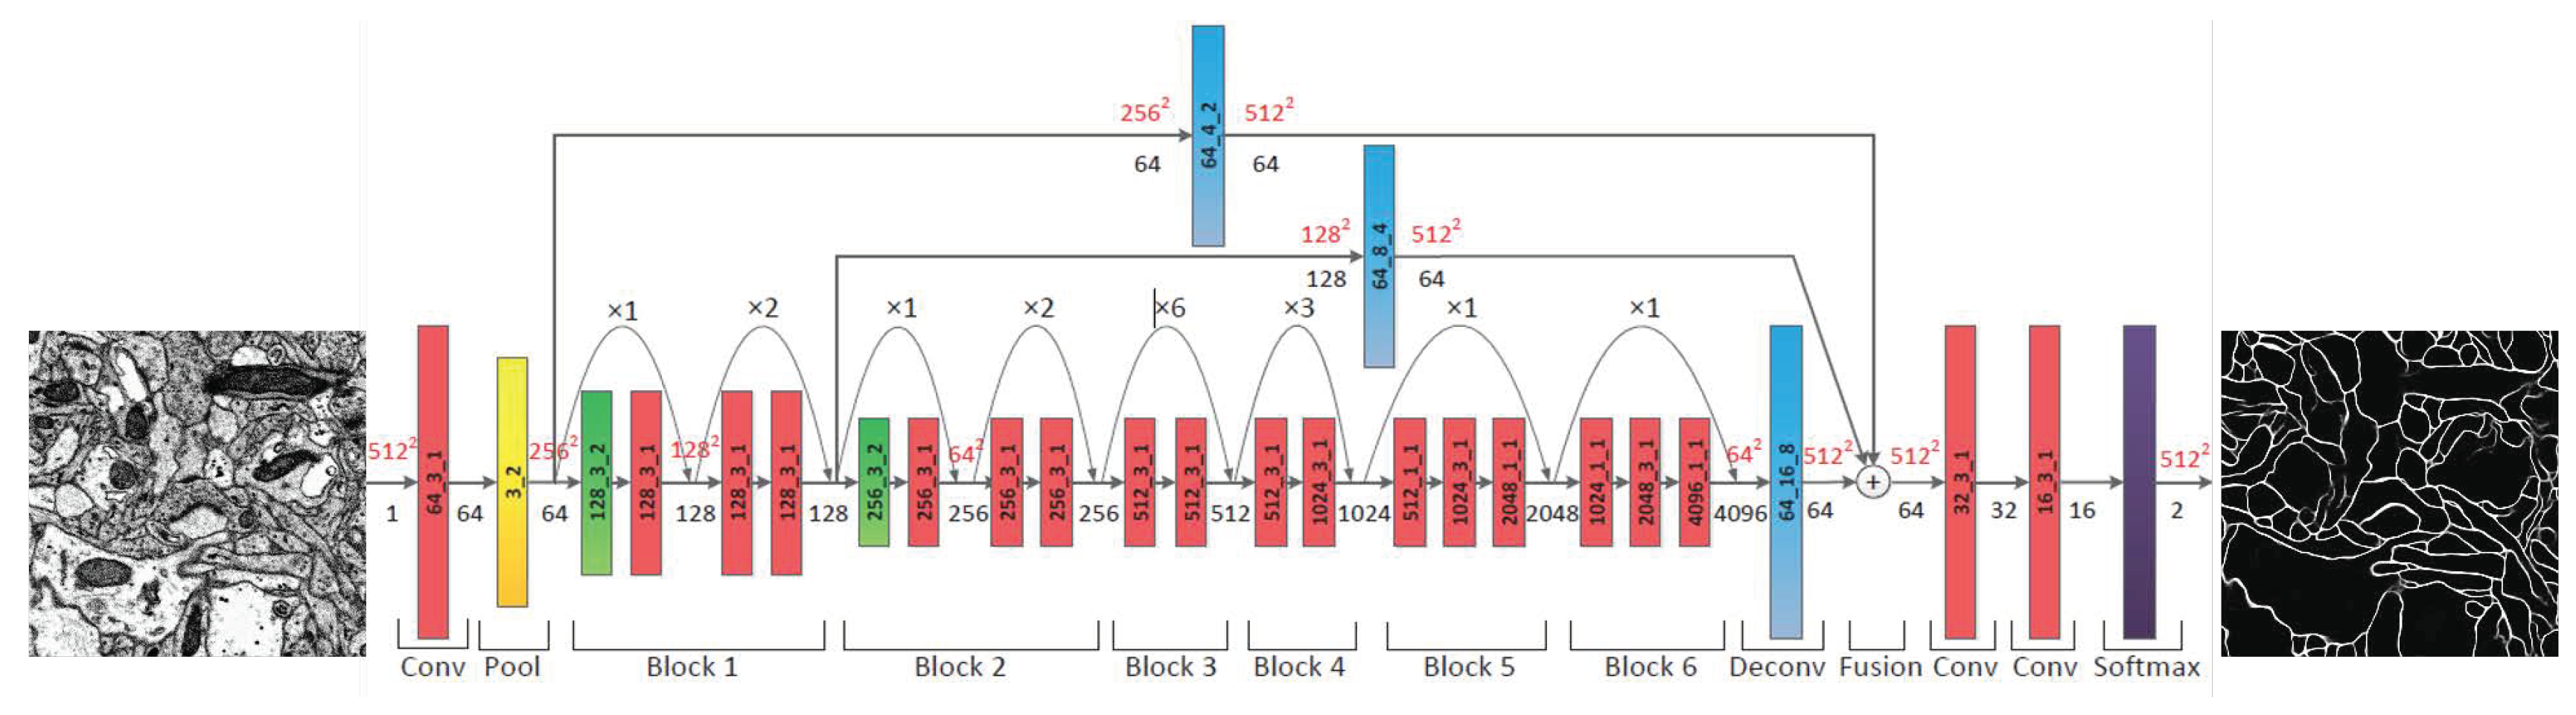

3.3. Segmentation of Neuron

3.3.1. Probability Map of the Neuronal Membrane